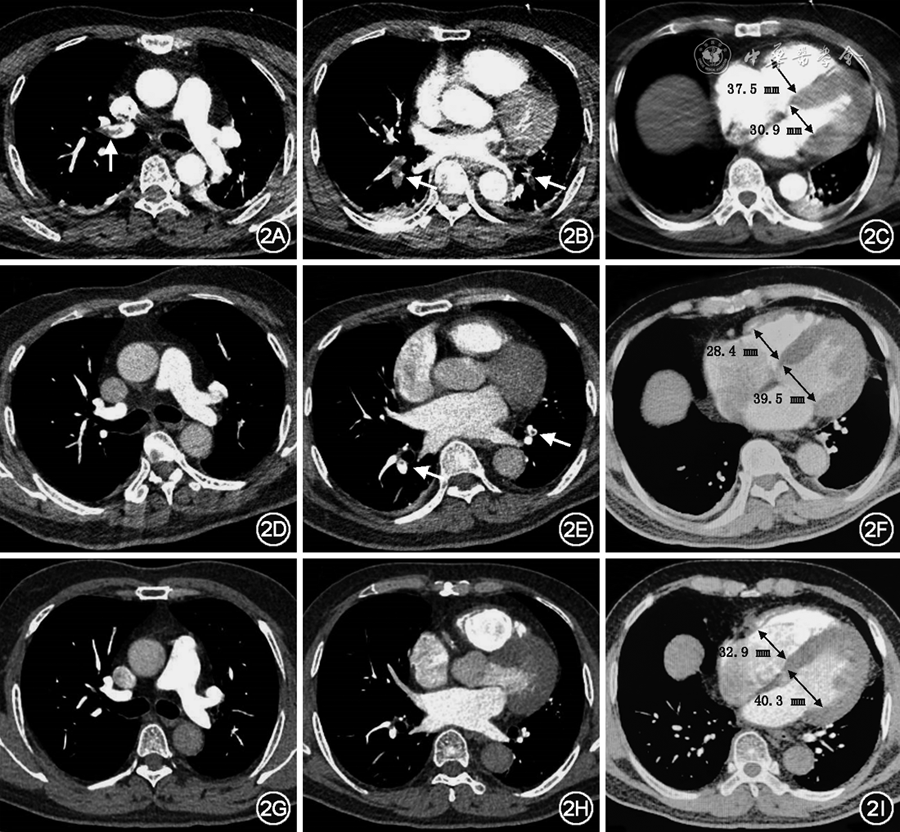

【病例报告】低剂量抗凝成功治疗高危肺栓塞1例

图片尺寸900x832